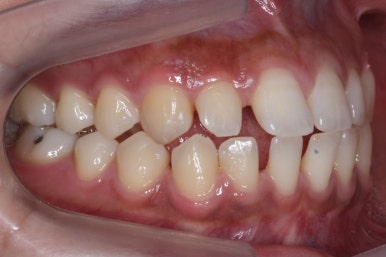

위 사진은 부산치아교정치과에 내원하셨을 대 당시의 입안 모습입니다.

치아들 사이에 전반적으로 틈이 많이 있는 상태입니다.

전반적으로 흩어져 있던 틈새를 특정 위치로 모으기 시작합니다.

앞니 사이의 없어진 틈은 대신 작은 억므니 부위로 모여져 갑니다.

앞니 사이의 틈이 이제 다 모아졌습니다.

다음 단계는 작은 어금니 부위에 모아진 틈을 없애는 것입니다. 앞서도 말씀을 드렸듯이 앞니의 앞-두로의 위치는 변화 시키면 안되기 때문에 오로지 어금니를 앞으로 당겨오면서 틈을 모아줘야 합니다.

어금니를 100% 당겨주는 방법은?

바로 미니스크류 입니다. 위 사진에서 화살표 부분이 바로 미니스크류 입니다.

뼈에 단단히 고정해 놓고 어금니를 앞으로 당겨오는데 사용을 하게 됩니다. 교정치료 후에는 제거하게 되며 긍방 뼈가 차기 때문에 별로 걱정은 하지 않으셔도 됩니다.

서서히 틈이 줄어들고 있는 것이 보입니다.

벌써 몇 군데는 틈이 다 모였습니다.